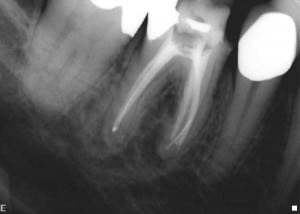

שבר פוצר הדסטרום בשן 46#.

שאלה: אולי זה לא מקובל אבל אני מרשה לעצמי לבקש את חוות דעתך על שן 46 של הגב' הצעירה (גילה  36). טיפול השרש  נעשה על ידי בכמה ישיבות עקב "הצלחתי" לשבור הדסטרום בתעלה מזיולינגואל. לא הצלחתי להוציא את החלק השבור, אך לדעתי עקפתי אותו והגעתי למלוי סביר. בתעלות הדיסטאליות המתחברות יצא מעט קצר. השן אינה סיפטומאטית כלל, עברה הורדה מגובה ונמצאת מאז במעקב סדיר עם סתימה זמנית. הייתי שמח לקבל ממך יעוץ לגבי דעתך על 46. אם אינך חושב שאתה מעוניין לתת  לי חוות דעת בלי לראות את המתרפאה, גם זה בסדר מצידי. תודה תשובה: אשמח לתת את חוות דעתי לפי הצילומים כפי שאוכל. אם ניבחן את הצילומים נוכל לראות הופעה של דלקת סב-שורשית. יש לציין מספר נקודות חשובות.

• הפוצר נשבר בקצה התעלה ולכן לא מומלץ להוציאו. אני גם לא ממליץ לנסות ולעקוף (אלא אם כן הדבר מצליח בקלות) וזאת עקב סיכון לטרנספורטציה של התעלה כפי שניתן לראות בצילום של סיום טיפול השורש. ניתן לראות הארכת אורך העבודה אך בסטייה מציר התעלה המלא בפוצר השבור. במקרה זה היה כדאי לאטום עד המכשיר ולנסות להגיע לאפקס (שלעתים הוא משותף לשתי התעלות) דרך התעלה השנייה. המחקרים מראים שהפרוגנוזה במצב הנ"ל (ללא דלקת סב-שורשית) טובה מאד.

• שחזור זמני מיועד בדר"כ לתקופה קצרה. הקונצנזוס היום הוא לחדש שן עם שחזור זמני מעל 3 חודשים. הסיבה היא דלף שולי. לכן הייתי ממליץ למרות שבירת הפוצר, לבצע מבנה קבוע וכתר זמני מותאם היטב. האיטום הכותרתי הוא קריטי להצלחת הטיפול. יתכן והפוצר השבור אינו הסיבה להתפתחות הדלקת אלא השחזור זמני שדלף לאורך תקופה ארוכה.

ניתן לשמר שן זו אך הדבר כרוך במספר טיפולים ובעלויות. יש לבצע חידוש טיפול שורש מבנה וכתר זמני. לאחר מכן במידה ולא יהיה ריפוי יש צורך באפיסקטומי. שני הטיפולים יחדיו נותניום להערכתי סיכויי הצלחה טובים מאד אך לא 100%. לכן חשוב ליידע את המטופל/ת ולקבל את הסכמתו/ה. במידה והמתרפא/ה אינה מעוניינת לבצע את הטיפולים הנ"ל ניתן כמובן לעקור ולבצע שתל. בהצלחה…